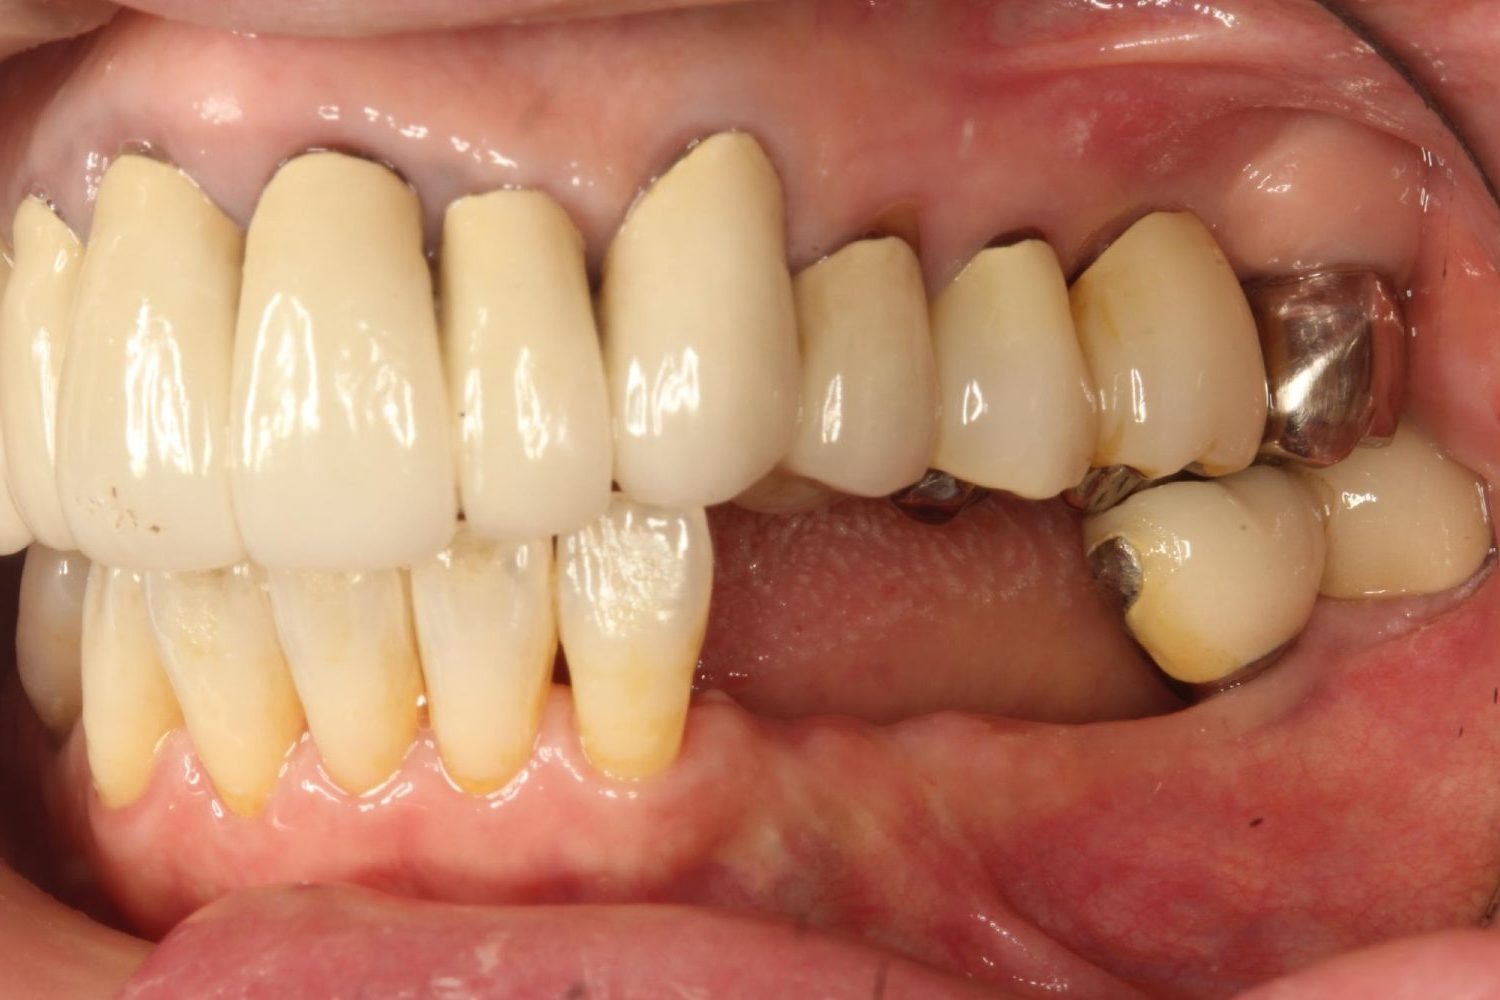

インプラント治療の症例紹介⑤

Before

After

主訴

歯肉腫脹、咬めるようにしたい

治療内容

重度歯周病により全ての残存歯保存不可能な状態。上下顎ボーンアンカードブリッジによる咬合再構成。

治療費

12,621,400円(税込)

治療期間

22ヶ月

通院回数

28回

想定されたリスク

※上部構造の形態が複雑になるため清掃が難しくなる、インプラント周囲炎の恐れがありました。

濱 仁隆先生

浜歯科

上顎8本下顎7本のインプラント体埋入によるボーンアンカードブリッジ。